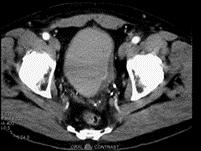

问题 男,55岁,血尿半月余,请根据其影像,判断其最可能的诊断 ( )

选项 A、膀胱憩室伴感染 B、慢性膀胱炎 C、膀胱癌 D、膀胱憩室 E、膀胱结石

答案 C